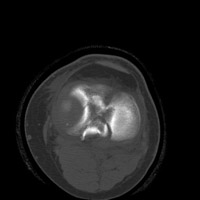

- Click on the image for a larger versionDAxial CT. This image from a different patient at the level of the tibial plateau demonstrates a fracture of the tibial spine.